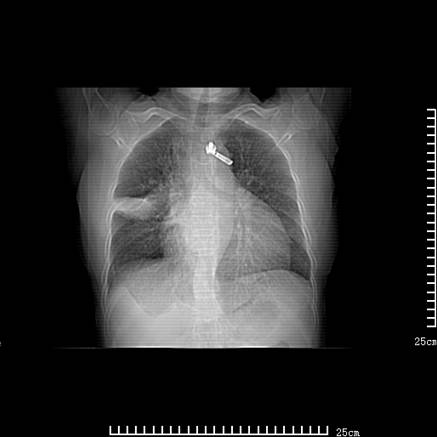

女,王某,58岁,咳嗽三个月余,基层医院二个月前诊为肺结核,用抗结核药二个月无明显疗效。

心包积液致肺瘀血.右侧周围型肺癌伴肺内转移,中间裂积液,叶间胸膜肥厚.右上肺大泡,右侧胸膜肥厚.

双肺继发型tb,心功能不全并肺淤血、心包、双侧叶间裂积液,肺大泡,右下胸膜肥厚钙化。

支持  双肺继发型tb,心功能不全并肺淤血、心包、双侧叶间裂积液,肺大泡,右下胸膜肥厚钙化。